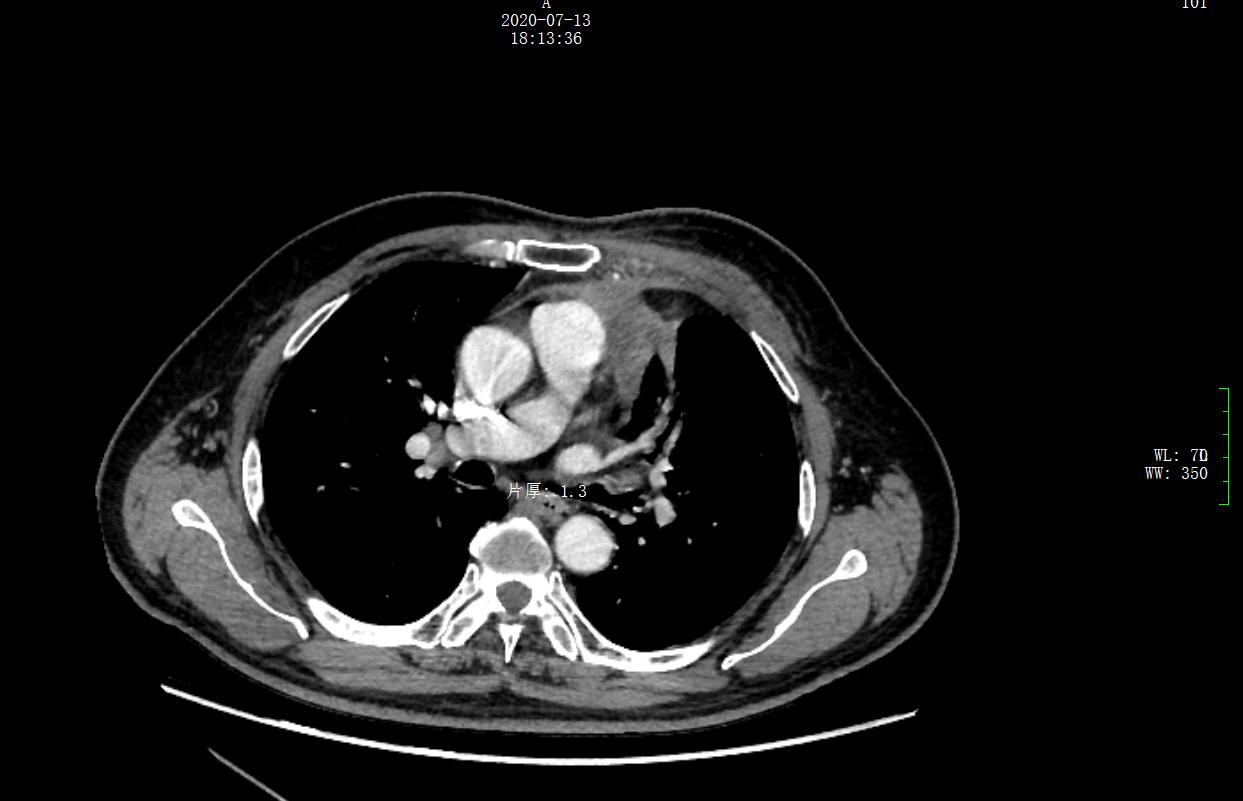

放疗结束后11个月(2020年7月)患者返院复查影像学,未发现局部复发与远处转移,左纵隔病灶及转移淋巴结明显缩小